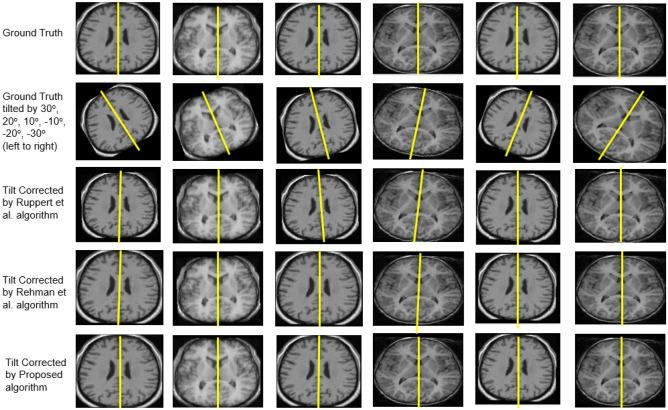

In a general scenario, the brain images acquired from magnetic resonance imaging (MRI) may experience tilt, distorting brain MR images. The tilt experienced by the brain MR images may result in misalignment during image registration for medical applications. Manually correcting (or estimating) the tilt on a large scale is time-consuming, expensive, and needs brain anatomy expertise. Thus, there is a need for an automatic way of performing tilt correction in three orthogonal directions (X, Y, Z). The proposed work aims to correct the tilt automatically by measuring the pitch angle, yaw angle, and roll angle in X-axis, Z-axis, and Y-axis, respectively. For correction of the tilt around the Z-axis (pointing to the superior direction), image processing techniques, principal component analysis, and similarity measures are used. Also, for correction of the tilt around the X-axis (pointing to the right direction), morphological operations, and tilt correction around the Y-axis (pointing to the anterior direction), orthogonal regression is used. The proposed approach was applied to adjust the tilt observed in the T1- and T2-weighted MR images. The simulation study with the proposed algorithm yielded an error of 0.40 ± 0.09°, and it outperformed the other existing studies. The tilt angle (in degrees) obtained is ranged from 6.2 ± 3.94, 2.35 ± 2.61, and 5 ± 4.36 in X-, Z-, and Y-directions, respectively, by using the proposed algorithm. The proposed work corrects the tilt more accurately and robustly when compared with existing studies.

在一般情况下,从磁共振成像(MRI)获得的脑图像可能会倾斜,扭曲脑 MRI 图像。脑 MRI 图像的倾斜可能会导致在医学应用的图像配准过程中出现对位不准。手动(或估计)大范围的倾斜非常耗时、昂贵,并且需要脑部解剖学专业知识。因此,需要一种自动的方法来在三个正交方向(X、Y、Z)上进行倾斜校正。本工作旨在通过分别测量 X 轴、Z 轴和 Y 轴上的俯仰角、偏航角和滚动角来自动校正倾斜。对于围绕 Z 轴(指向上方)的倾斜校正(指向上方),使用图像处理技术、主成分分析和相似性度量。此外,对于围绕 X 轴(指向右侧)的倾斜校正(指向右侧),使用形态学操作和围绕 Y 轴(指向前方)的倾斜校正(指向前方),使用正交回归。该方法应用于调整 T1 和 T2 加权 MRI 中观察到的倾斜。该算法的模拟研究产生的误差为 0.40±0.09°,优于其他现有研究。通过使用该算法,在 X、Z 和 Y 方向上获得的倾斜角度(以度为单位)分别为 6.2±3.94、2.35±2.61 和 5±4.36。与现有研究相比,该方法能更准确、更稳健地校正倾斜。